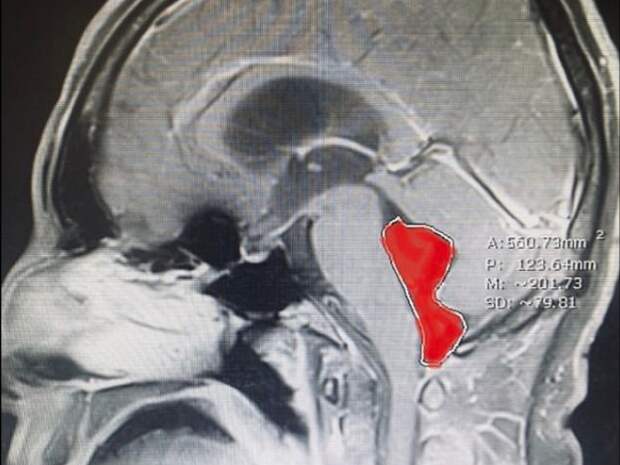

Мужчина из Техаса несколько месяцев мучился от головной боли, настолько сильной, что его рвало. Также он столкнулся и с внезапной потерей сознания. Обследование показало, что в его мозге имеется некое образование длиной около 4 см, однако тесты исключили опухоль.

Дальнейшие анализы установили: в мозге мужчины находится свиной цепень. Врачи удалили его в ходе операции. Сейчас пациент полностью здоров.Личинка паразита, скорее всего, попал в организм пациента еще около 10 лет назад, когда он ездил в Мексику и ел там плохо прожаренную свинину. Все это время он медленно рос. Обычно свиной цепень поражает кишечник, но может добраться и до головы, поселившись в глазах или мозге.